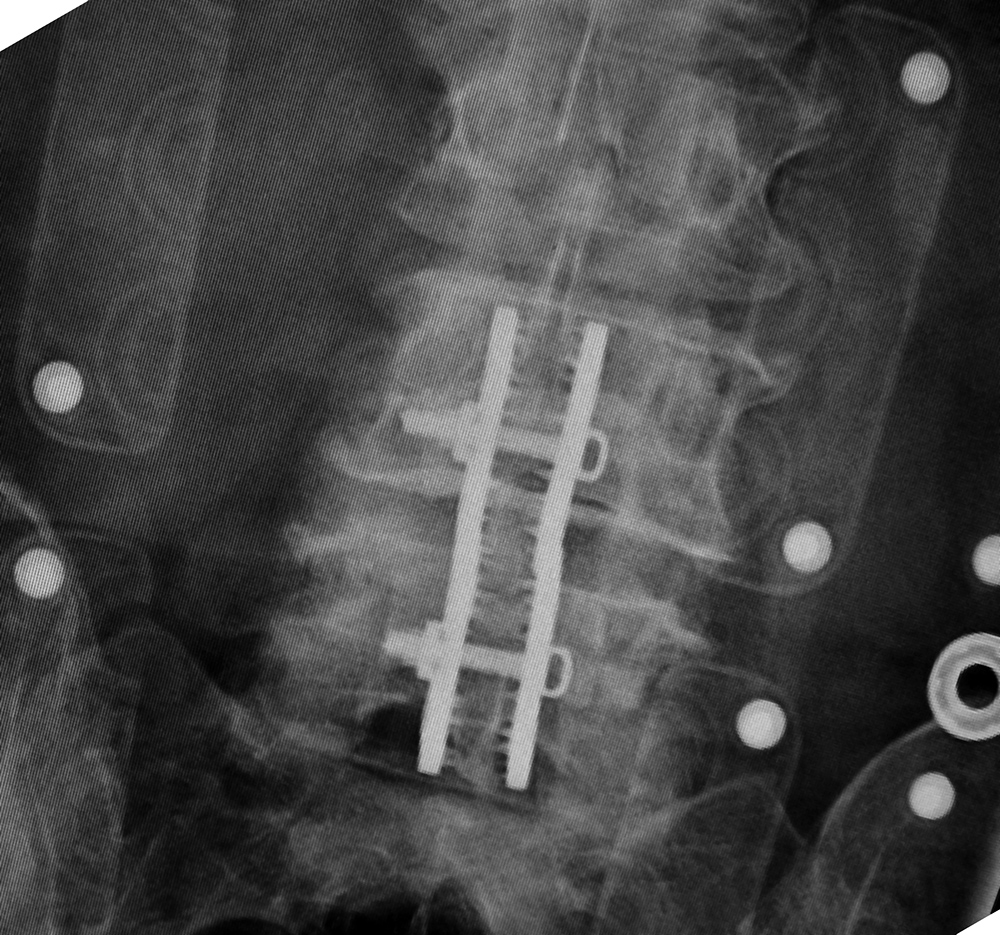

| Harms vertebral cage (AP view) |

| There is a vertebral cage and side plate and screws in the lower thoracic spine for treatment of a spinal tumor. From Hunter, 1994 |

| Vertebral corpectomy with vertebral cage and left lateral side plate |